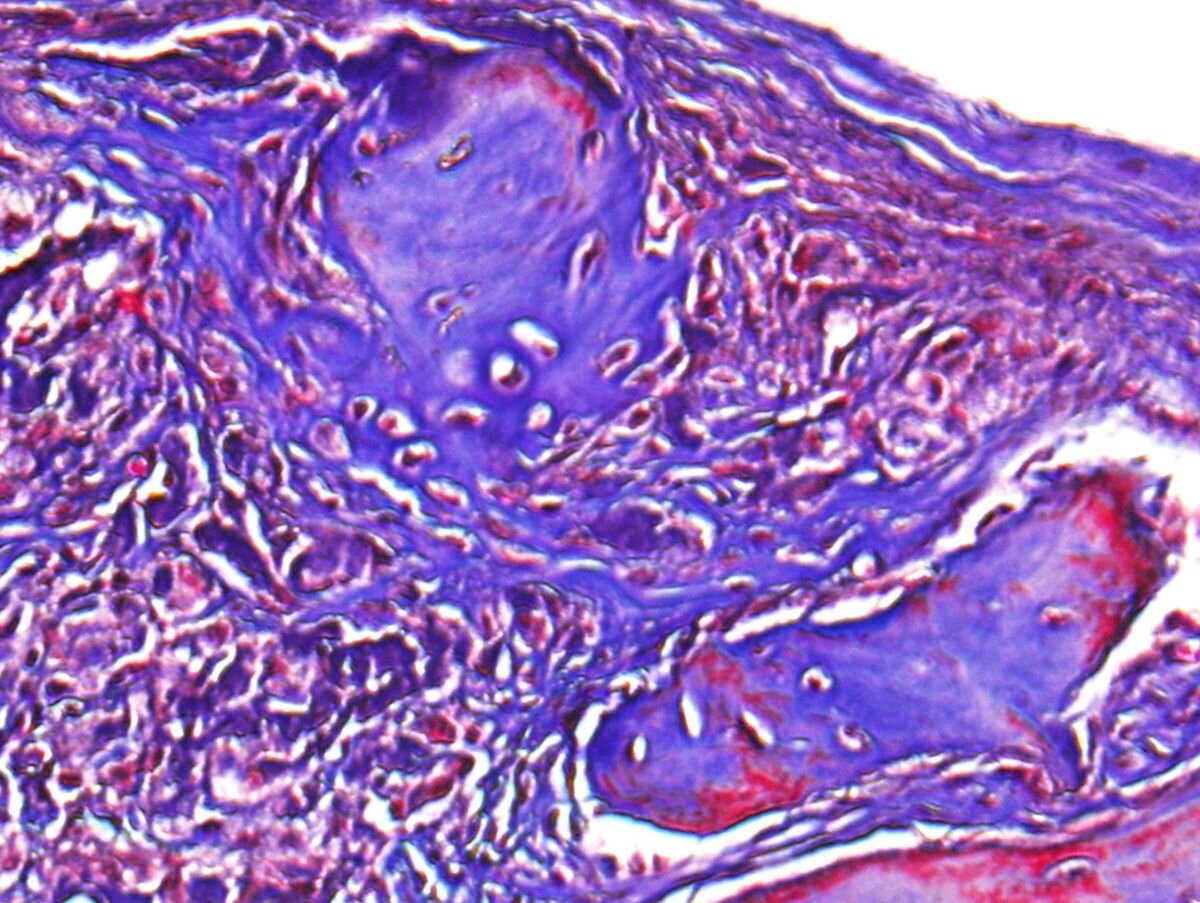

یک تصویر میکروسکوپی از استخوان بازسازی شده در نقص جمجمه در موش. اعتبار: دانشگاه کالیفرنیا، لس آنجلس

مدل موش دارای نقص جمجمه غیر شفابخش بود که محققان هیدروژل تقویت شده خاک رس خود را تزریق کردند. پس از شش هفته، آنها دریافتند که این مدل بهبودی استخوان را از طریق مهاجرت و رشد سلولهای بنیادی طبیعی خود نشان می دهد.